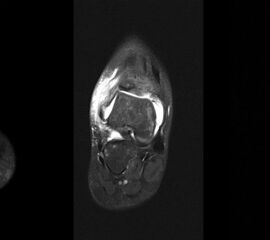

MRT

Die Kernspintomographie hat ihre Stärke in der Darstellung von Weichteilverletzungen. Insbesondere Verletzungen der Wachstumsfuge, des Periosts und der Bänder lassen sich gut visualisieren. Nachteilig ist die Untersuchungsdauer von 20-30 Minuten. Bleibt das Kind während dieser Zeit nicht ruhig liegen, kommt es zu Bewegungsartefakten, welche die Beurteilbarkeit der Bilder beeinträchtigen.

Os subfibulare

Multiple laminäre Ausrisse des fibularen Bandapparats aus der Fibulaspitze können zur Entwicklung eines Os subfibulare führen. Das Os subfibulare findet sich unterhalb der Fibulaspitze ventral der Peronealsehnen. Ohne Schmerzsymptomatik bzw. Aktivierung im MRT hat Das Os subfibulare keinen Krankheitswert. Ein mobiles Os subfibulare führt zu einer lokalen mechanischen Reizung teilweise in Verbindung mit einer Instabilität des Sprunggelenks. Im MRT zeigt sich eine Aktivierung des instabilen Areals. Bei anhaltenden Schmerzen besteht die Behandlung in einer operativen Entfernung des Knochens mit Refixation des Kapselbandapparats.